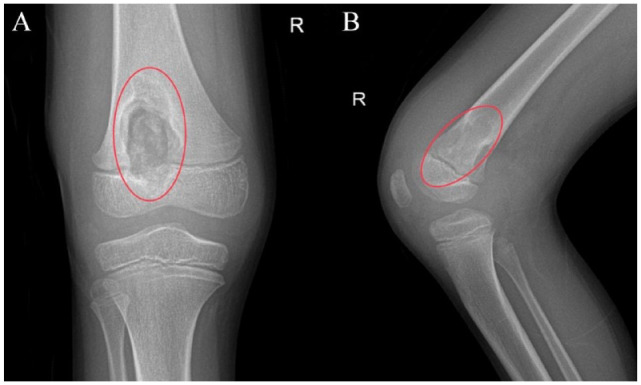

Case presentation: We report a rare case of a 9-year-old male diagnosed with right knee tuberculosis after enduring severe symptoms for several months. Despite multiple negative biopsies and aspirates during initial debridement surgeries, a biopsy taken 6 months later confirmed the presence of Mycobacterium tuberculosis (MTB). The patient was subsequently treated with debridement and anti-tubercular therapy.